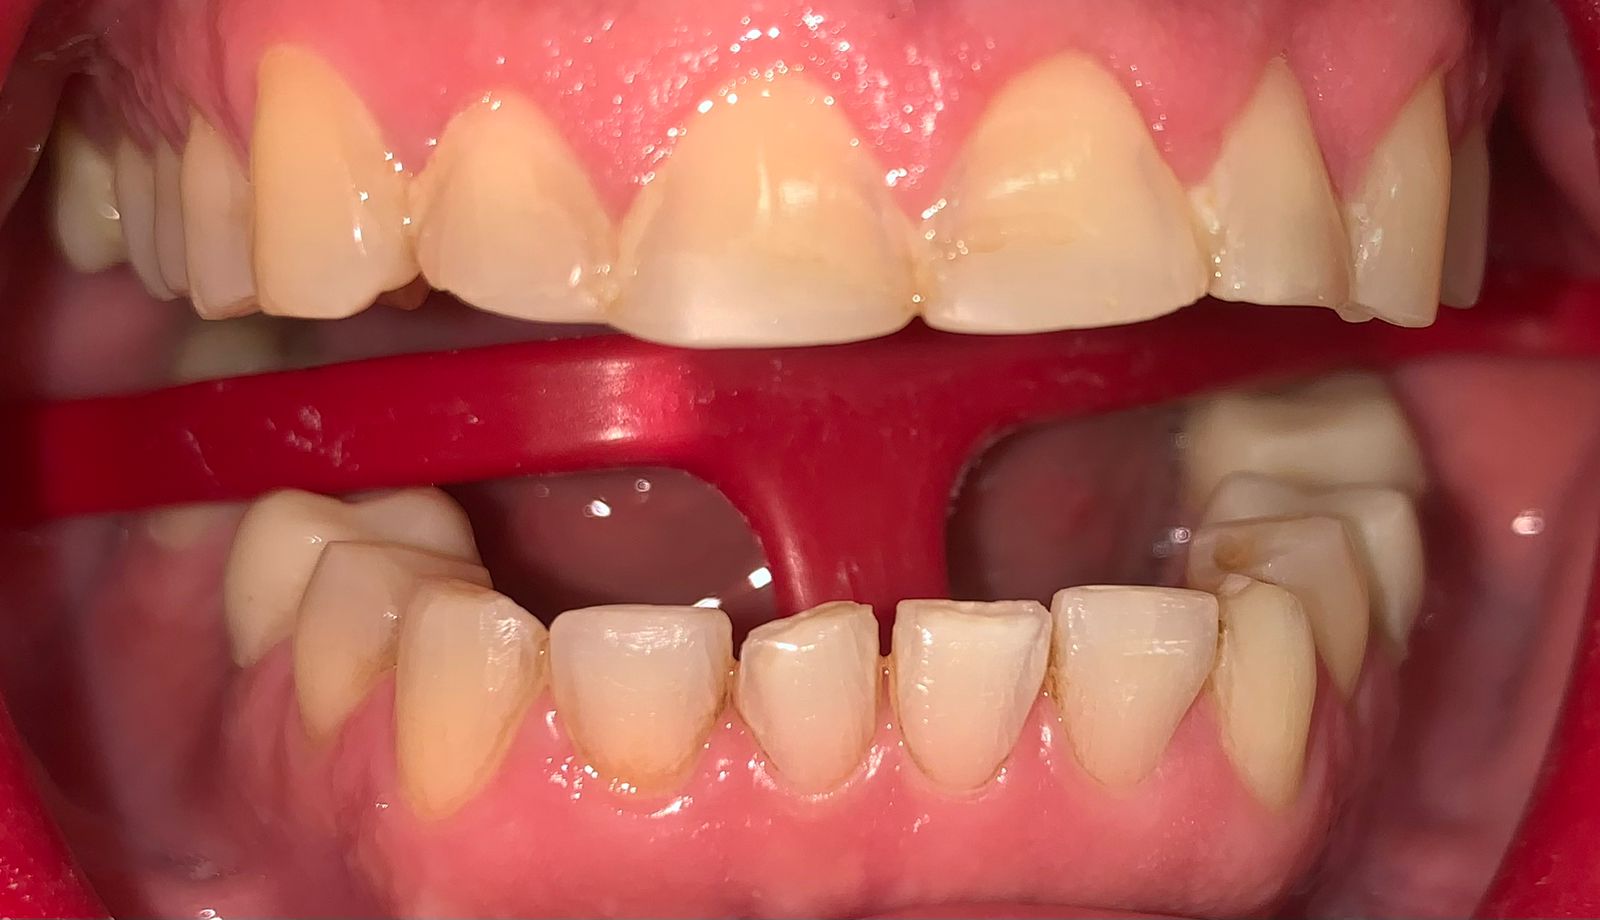

Fase 3: Diagnóstico inicial maxilar superior

Fase 3

Rehabilitación Oral - Diagnóstico Superior

Estado inicial del paciente con ausencia dental severa en maxilar superior, afectando función masticatoria y estética.